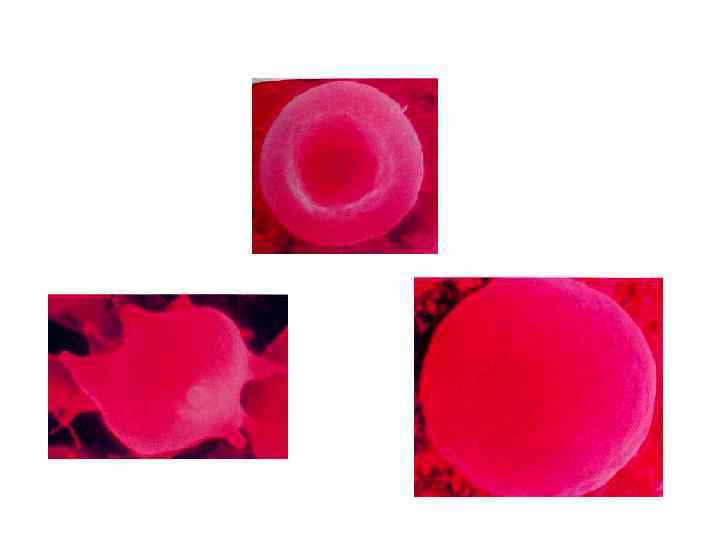

• Эритроциты в крови здорового человека преимущественно (до 70 %) имеют форму двояковогнутого диска. • Поверхность диска в 1, 7 раза больше, чем поверхность тела такого же объема, но сферической формы.

• Эритроциты в крови здорового человека преимущественно (до 70 %) имеют форму двояковогнутого диска. • Поверхность диска в 1, 7 раза больше, чем поверхность тела такого же объема, но сферической формы.

эритроциты • Нормохромные - Fi = 0, 7 -1, 1 • Гипохромные - Fi менее 0, 7 • Гиперхромные - Fi более 1, 1 • Гиперхромные эритроциты увеличиваются в размерах

эритроциты • Нормохромные - Fi = 0, 7 -1, 1 • Гипохромные - Fi менее 0, 7 • Гиперхромные - Fi более 1, 1 • Гиперхромные эритроциты увеличиваются в размерах